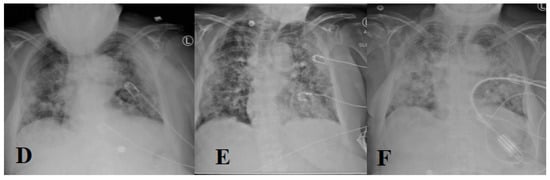

- Yasin, R.; Gouda, W. Chest X-ray findings monitoring COVID-19 disease course and severity. Egypt. J. Radiol. Nucl. Med. 2020, 51, 1–18. [Google Scholar] [CrossRef]

- Amyar, A.; Modzelewski, R.; Ruan, S. Multi-Task Deep Learning Based CT Imaging Analysis for Covid-19: Classification and Segmentation General Electric Healthcare; University of Rouen: Rouen, France, 2020; pp. 2–8. [Google Scholar]